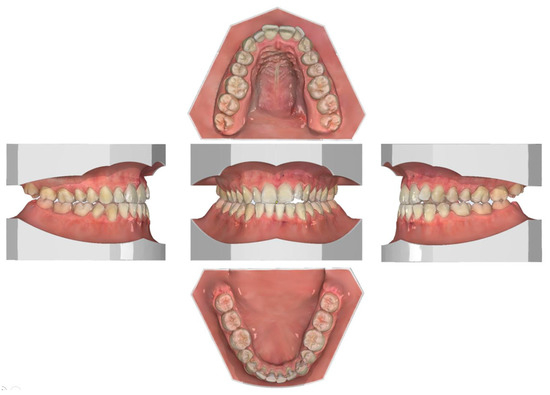

2.1. Diagnosis and Individual Treatment Planning

2.2. Clinical Preparations